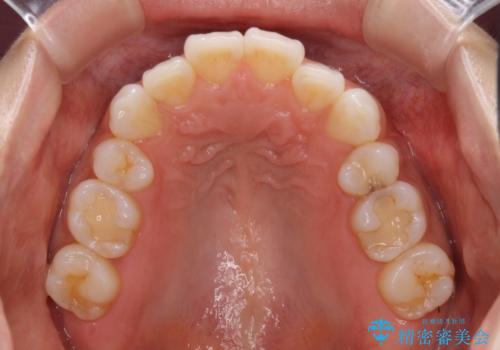

矯正治療の後戻り インビザラインによる再矯正治療

- 以前ワイヤー装置にて行った抜歯矯正の後戻りを気にして来院された患者様です。

前歯のデコボコにより、やや口元が突出した印象となっていたため、口元も引っ込めることとしました。

上下顎前歯に積極的にIPR(歯と歯の間を削る)を行い、インビザラインを用いて治療していくこととしました。

デコボコが解消されるのはもちろんのこと、突出感のあった前歯を引っ込めることができ、患者様には大変満足していただきました。